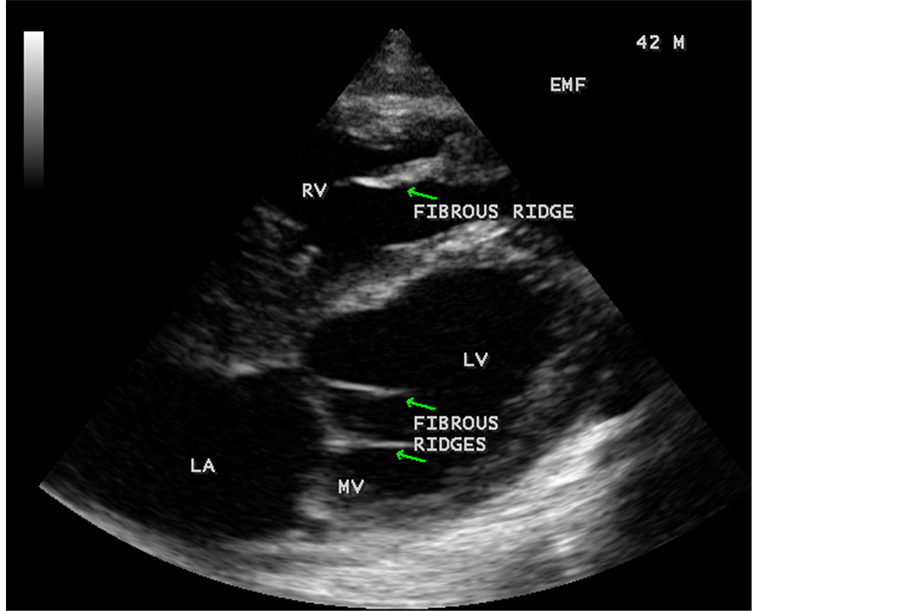

Figure 45. Endomyocardial fibrosis showing thickening of LV tendons seen as fibrous ridges as an initial manifestation of LV EMF in a 23-year-old male.

Figure 81. Tilted apical view showing the fibrous ridges of EMF in a 42-year-old male.

When the endocardium is replaced by collagenous fibrosis (consists of collagen deposition and fibroblast proliferation), the final fibrotic stage is reached after several years of disease activity. Fibrotic obliteration of the apices of the affected ventricles is the hallmark of the disorder and fibrosis involving the papillary muscles and chordae tendineae leading to atrioventricular valve distortion and regurgitation. In the left ventricle, the fibrosis extends from the apex to the posterior mitral leaflet, usually sparing the anterior mitral leaflet and outflow tract and cause PML (posterior mitral leaflet) distortion and regurgitation. Like the peculiar geographical distribution, the fibrotic endomyocardial involvement stops short of the ventricular outflow tract like a ridge [17] as shown in Figure 15, Figure 29, Figure 31, Figure 35 and Figure 45. The fibrotic tissue often creates a nidus for thrombus formation, which can be extensive. Atrial thrombi also occur and the right atrium may be aneurysmally dilated. Aneurysmal right atrium with spontaneous echo contrast was detected in a 32-year-old male as shown in Figure 36 ( [18] , Figure 3]). In addition, there are fibrosis and granular septation extending into the underlying myocardial tissue and myocyte hypertrophy is common [19] . Fibrotic process causes tethering of leaflets into ventricular walls and may mimic Ebstein’s malformation as shown in Figure 39 and Figure 66 [20] [21] . Fibrosis increases the stiffness of the heart, resulting restrictive physiology, AV (atrioventricular) valve regurgitation which has been linked to atrial arrhythmias such as atrial fibrillation as shown in Figure 19 and Figure 20 in a 62-year-old female. Atrial fibrillation has been reported in more than 30% of patients with EMF. Fibrosis impairs activation patterns of the conduction system and may provide substrate for wave breaks and reentry [22] . Fibrosis reduces conduction velocity and cause conduction abnormalities like junctional rhythms, heart blocks as shown in Figure 21 and Figure 22 in a 75-year- old female and atrioventricular conduction delay [23] .